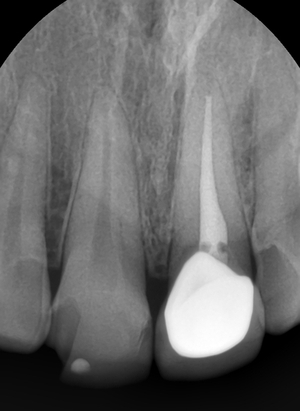

대문이 중 하나는 라미네이트, 하나는 신경치료 후 크라운이 되어있는 상태였습니다.

10년전에 하신 기존 보철물을 제거한 상태

위 사진은 잇몸절개 후 시간이 지나고, 기존 파절된 오래된 라미네이트와 오래된 크라운을 제거했으며

옆의 두 치아의 건강한 치아부분은 삭제하지 않고 충치부위만 삭제하고 찍은 사진입니다.

(치료 중간에 찍은 사진입니다)

기존에 10년전 다른 치과에서 치아삭제 라미네이트를 하셨기 때문에 라미네이트를 제거했을 때 치아가 삭제되어 있고

기존에 크라운이 되어있던 부위도 당연히 치아가 삭제된 상태입니다.